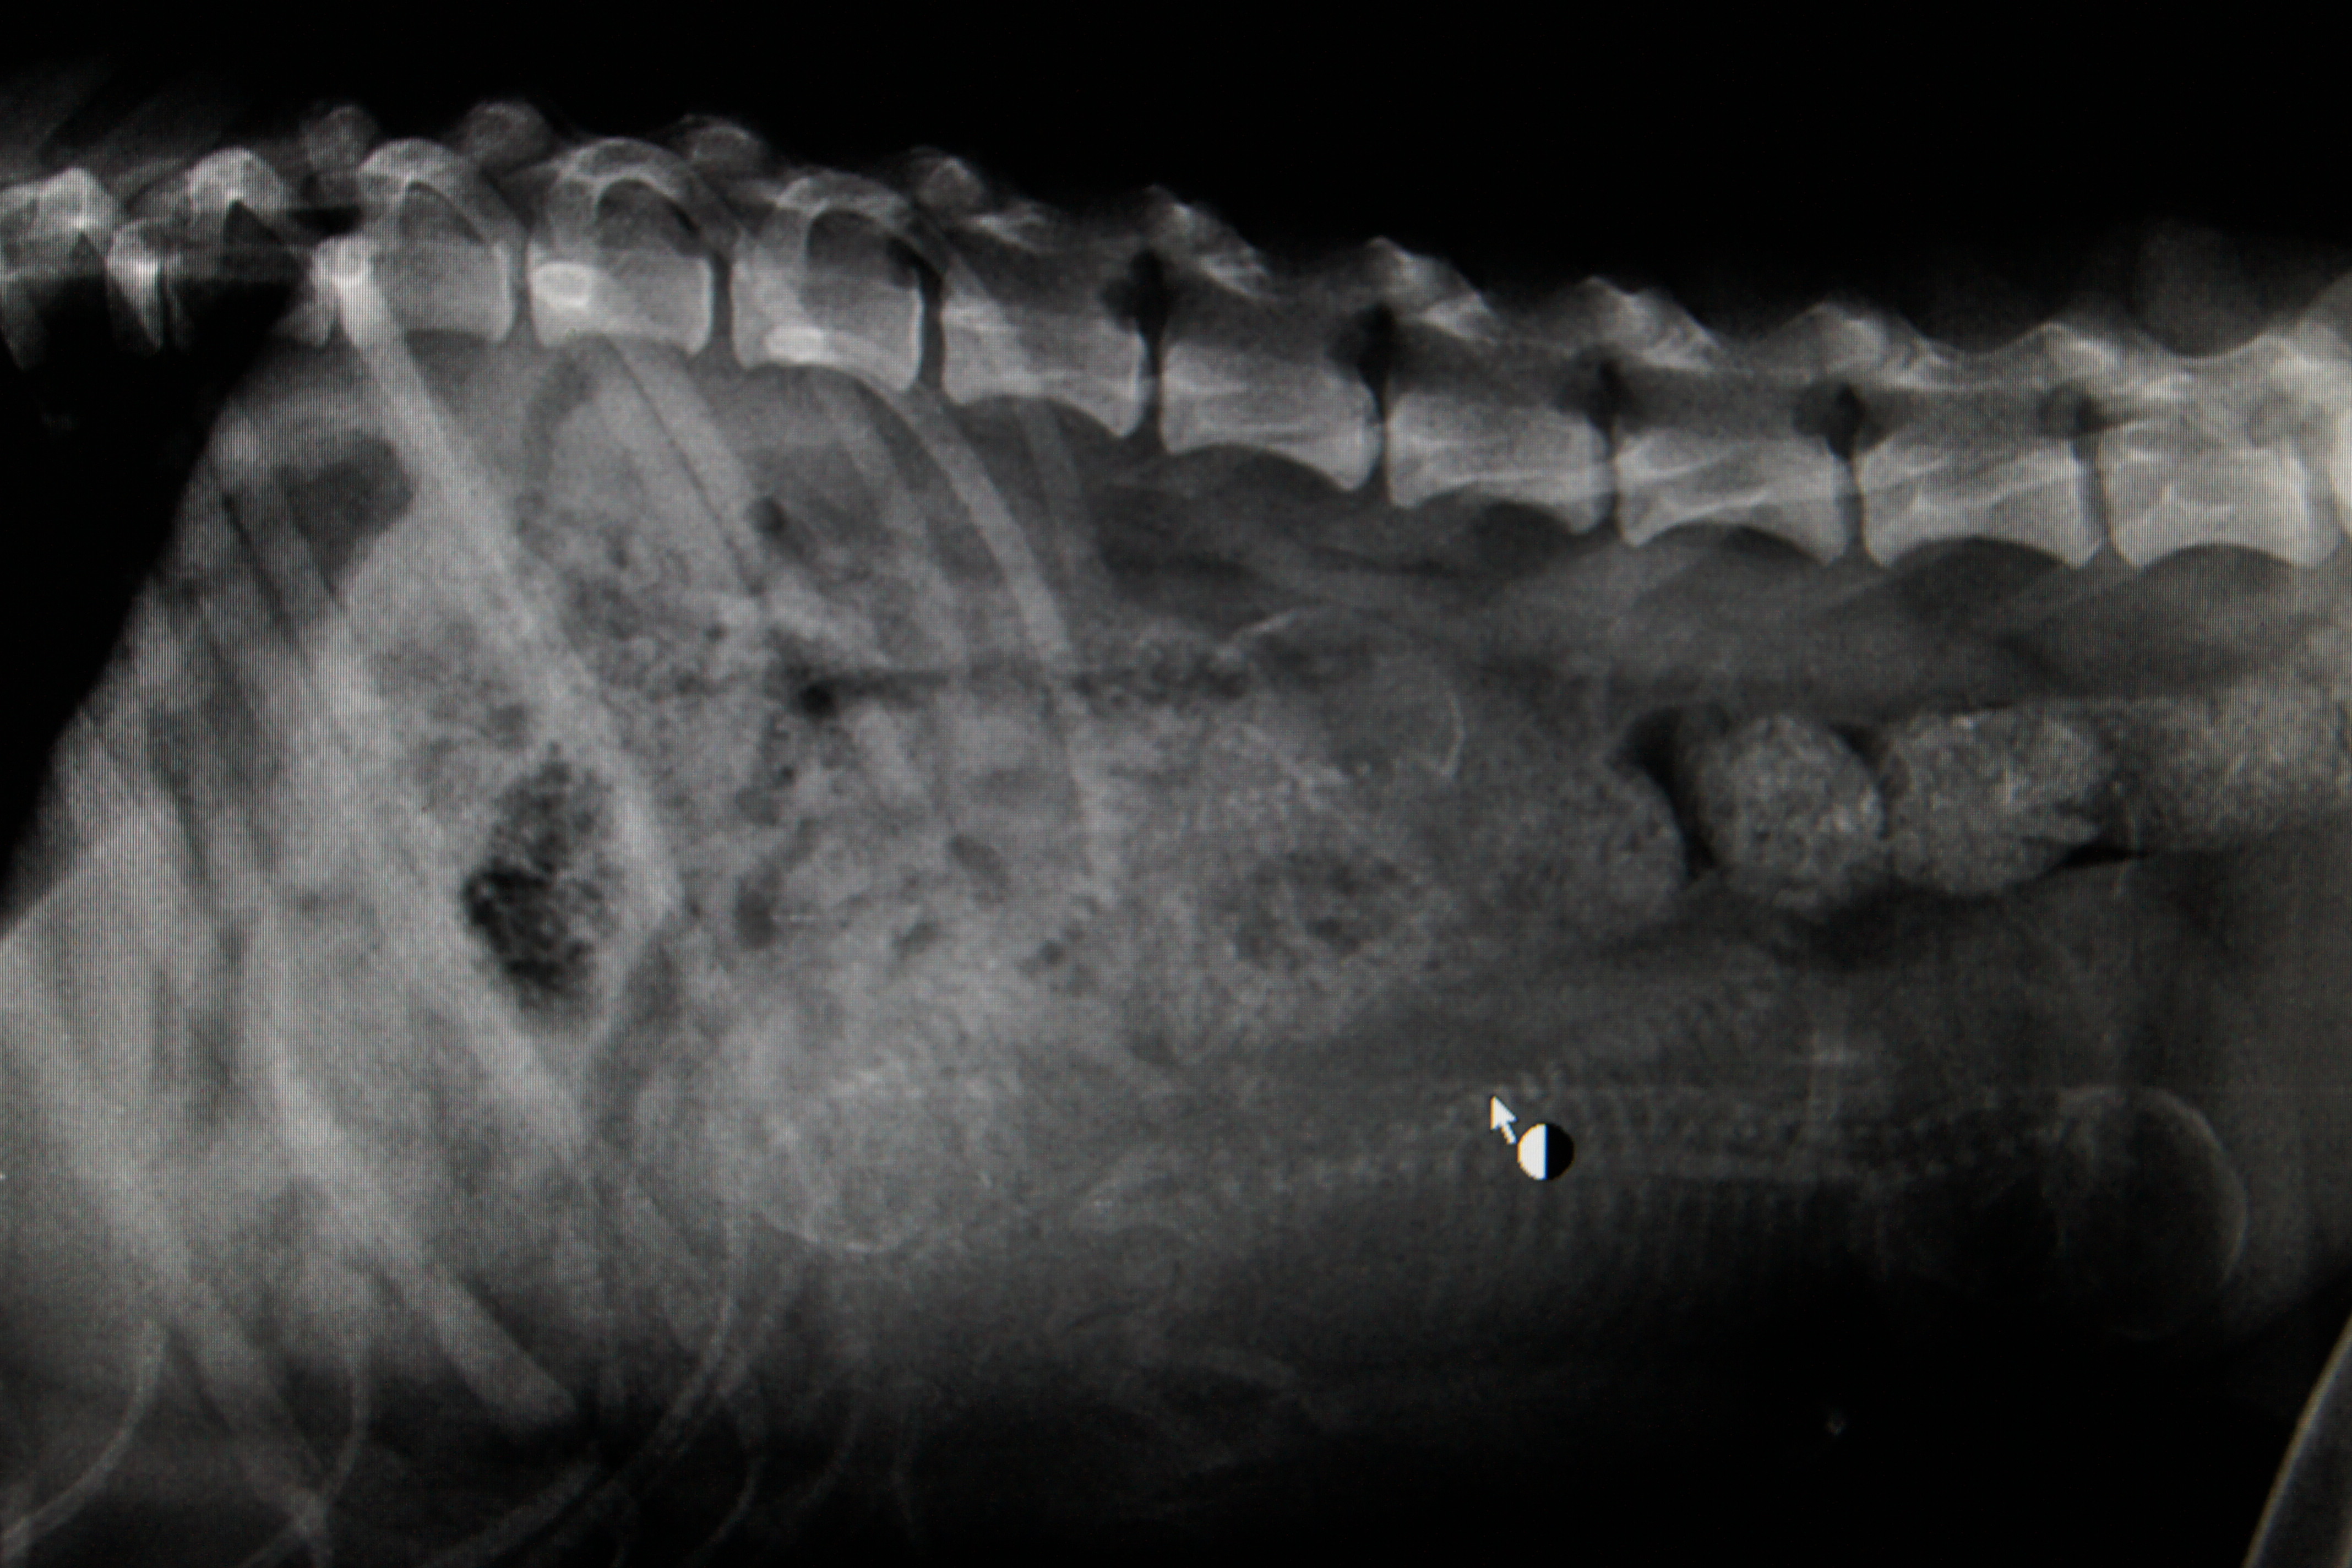

Ultralyd tatt i uke 5, var det antatt minst 4 valper. Rtg tatt ca 1 uke før mente veterinæren det var 3 valper, men jeg synes jeg ser 4 her:

Bilde er tatt liker etter valp nr 4.